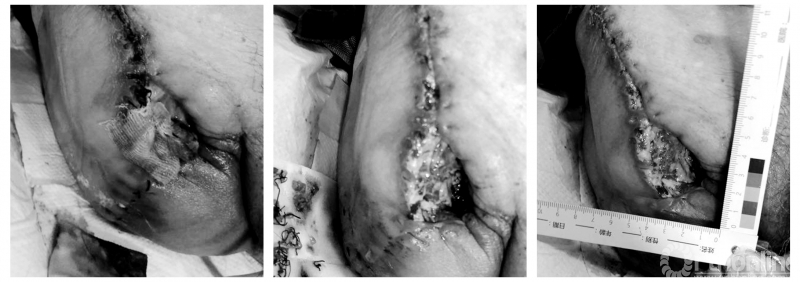

查体:右髋部可见15*10*cm大小人字形伤口,上下两头缝线伤口愈合好,中间对接处缝线伤口已裂开,可见5cm×6cm×3cm伤口,有黄绿色脓性分泌物流出伴恶臭。

(2)黄期(清创期)

具体采用外科清创及自体清创相结合的方式进行处理[4]。用0.9%生理盐水冲洗伤口,周围皮肤用碘伏消毒,用无菌剪刀外科清创法清掉黄色坏死组织后,伤口用银离子敷料+藻酸盐敷料填塞,银离子抗菌敷料为广谱抗菌敷料,它可以有效的去除细菌,为伤口愈合提供有利环境,从而快速控制感染,促进伤口愈合[5]。藻酸盐敷料可以吸收渗液,减少创面的渗出液 ,可以减少换药次数和对被服的污染[6]。二级敷料使用无菌纱布覆盖,隔天换药1次,直至坏死组织完全清除。

(3)红期(肉芽组织生长期)

于第16天清除黄色坏死组织,伤口基底可见100%红色新鲜肉芽组织,可见少量黄色清亮性渗液。为促进肉芽组织生长,给予0.9%生理盐水清洗伤口后,用康复新液纱条填塞伤口,外层使用无菌纱布敷料覆盖,根据渗液情况每天或者隔天换药一次[7]。

第32天打开伤口敷料见肉芽组织生长缓慢,给予自制简易负压封闭引流术,促进肉芽组织生长。用生理盐水清洗伤口后,无菌剪刀将一次性胃管前端采用螺旋型走向,每约0.5-1cm剪出一个孔径约0.5cm侧孔,一次性头皮针剪掉前端针头,凡士林油纱裁剪合适大小放置在伤口床内,再用无菌纱布将头皮针管前端及胃管包裹好放置于伤口床,上面覆盖两层无菌干纱布,周围用3M透明膜封闭。生理盐水连接输液器及头皮针接头冲洗,连接中心负压吸引装置,调节负压值为0.02-0.06MPa,观察透明膜内敷料经负压吸引后凹陷变硬、引流管内有液体吸出为吸引正常[8],5-7天更换一次。

(4)粉期(上皮爬行期)

第50天见新鲜肉芽组织填满伤口,边缘整齐,给予0.9%生理盐水清洗伤口后,贴泡沫敷料促进上皮爬行,5-7天换药一次,第61天伤口无疤痕愈合。